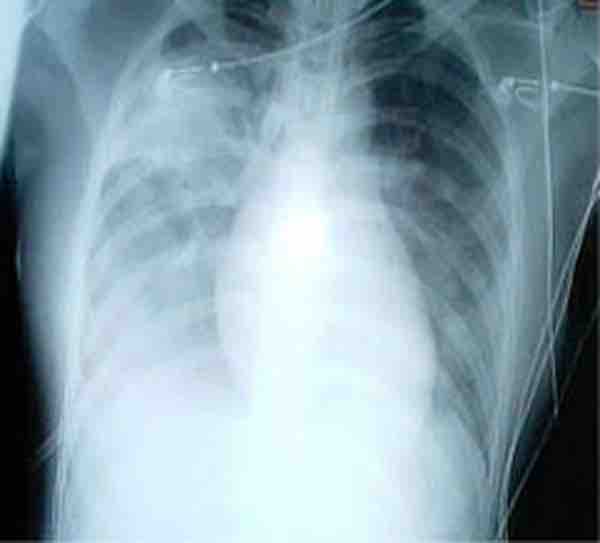

A chest x-ray showing increased opacity in both lungs, indicative of pneumonia, in a patient with SARS.